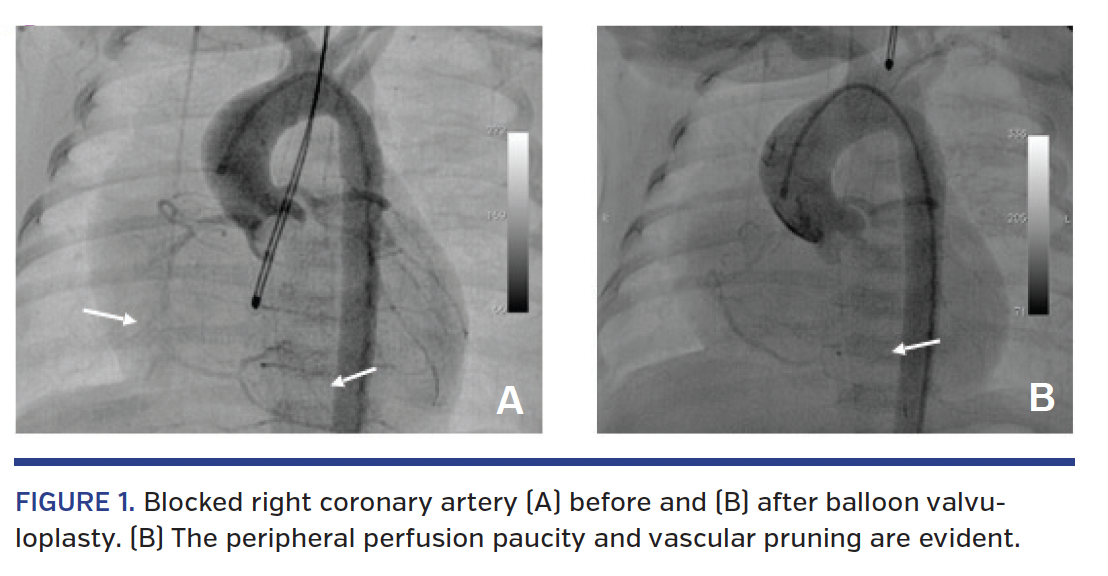

A 5-day-old term baby (weight, 3.5 kg) was transferred by air to our unit due to critical aortic stenosis (AS). Echocardiography showed severe left ventricular (LV) function impairment with diffuse LV hypokinesia and ejection fraction of 13%. The left atrium was moderately enlarged. The AS peak gradient was 70 mm Hg due to cusp fusion between the right and left coronary cusps. The newborn was taken to the cath lab, where right femoral artery access was easily obtained followed by heparin bolus of 50 IU/kg. Angiography of the ascending aorta showed a dysplastic, doom-shaped aortic valve with a negative flow jet toward the right anterolateral aortic wall and right coronary artery (RCA) occlusion at its mid segment, with its peripheral part reconstituted by collateral vessels from the left coronary artery connecting with the posterior descending artery (Figures 1A and 2A). Due to low systolic blood pressure (45 mm Hg) despite inotropic support with dopamine infusion, it was decided to proceed immediately with valvuloplasty and deal with the coronary occlusion afterward. During routine pre-valvuloplasty testing with pacing at 180 bpm, the patient developed ventricular fibrillation and was successfully cardioverted. Aortic valve annulus measured 7 mm; hence, balloon valvuloplasty followed, using a 7 x 2 Tyshak mini balloon catheter (B. Braun) with rapid pacing at 150 bpm. Disappearance of the balloon waist was noted and final hemodynamic peak gradient measured 15 mm Hg with no aortic regurgitation as seen on the repeat aortic angiogram. Interestingly, the angiogram also showed completely restored RCA perfusion, but acute pruning of the distal coronary network, implying embolization of the thrombus distally (Figure 1B).